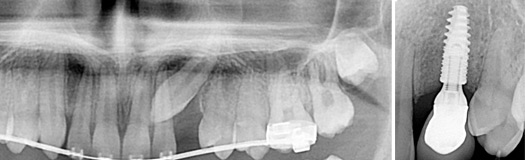

J’ai juste une dent à extraire c’est tout.

Solution : on l’enlève et on place un implant pour la remplacer tout simplement.

La dent sera extraite et si cela est possible, la racine artificielle sera placée DE SUITE après l’extraction permettant de gagner du temps sur la cicatrisation.

Une molaire du bas perdue serra remplacée par un implant.

Une molaire du haut perdue remplacée par une racine artificielle.